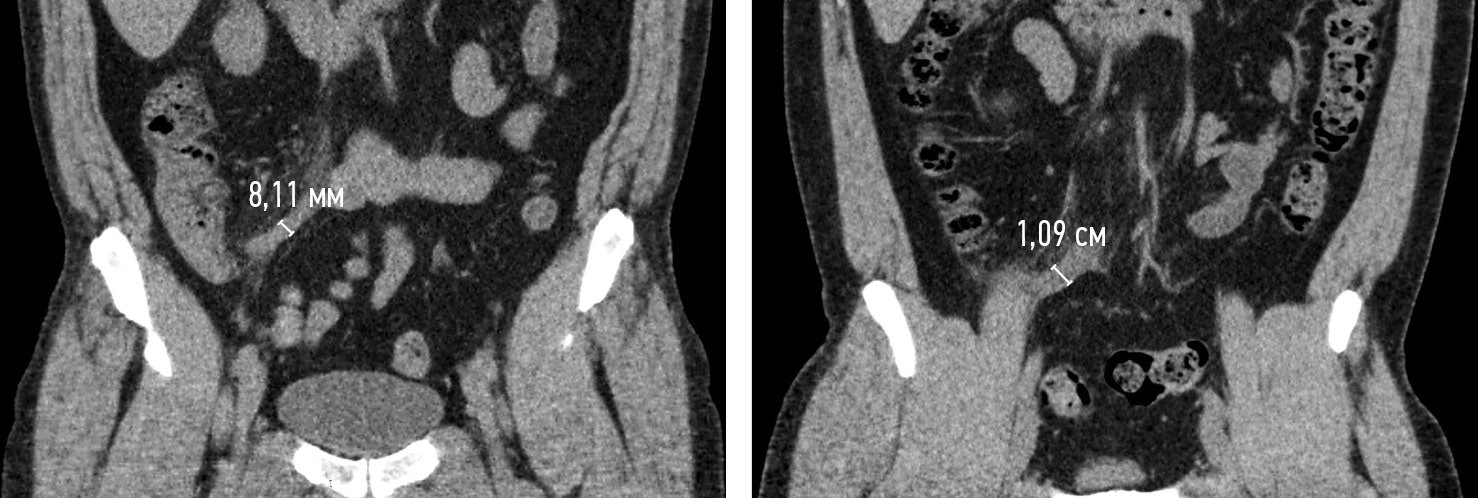

Неоднозначно мнение по поводу числового показателя увеличения диаметра. Традиционным пороговым значением для визуализационной диагностики ОА (УЗИ, КТ, МРТ) является диаметр 6–7 мм (рис. 4) [3, 16, 19].

Рис. 4. КТ-изображения двух пациентов с острым аппендицитом во фронтальной плоскости в нативную фазу с указанием диаметров аппендикулярных отростков

Fig. 4. CT images of two patients with acute appendicitis in the frontal plane in the native phase, indicating the diameters of the appendicular processes

Отдельные авторы рекомендуют использовать пороговый диаметр 9,25 мм, опираясь на проведенный анализ литературы и обосновывая это тем, что диаметр нормального аппендикса может составлять более 6 мм [14]. В 2015 г. Trout A.T. et al. сообщили о более высокой точности трехкатегориальной интерпретации диаметра аппендикса при УЗИ в диагностике ОА у детей, чем традиционное пороговое значение 6 мм [23]. По их данным, ОА присутствовал в 2,6, 65 и 96 % соответственно при диаметрах аппендикса до 6 мм, от 6 до 8 и свыше 8 мм. Авторы статьи считают, что диагноз ОА не следует ставить только на основании диаметра, поскольку это приведет к ложноположительным результатам (рис. 5, а, б) [23].